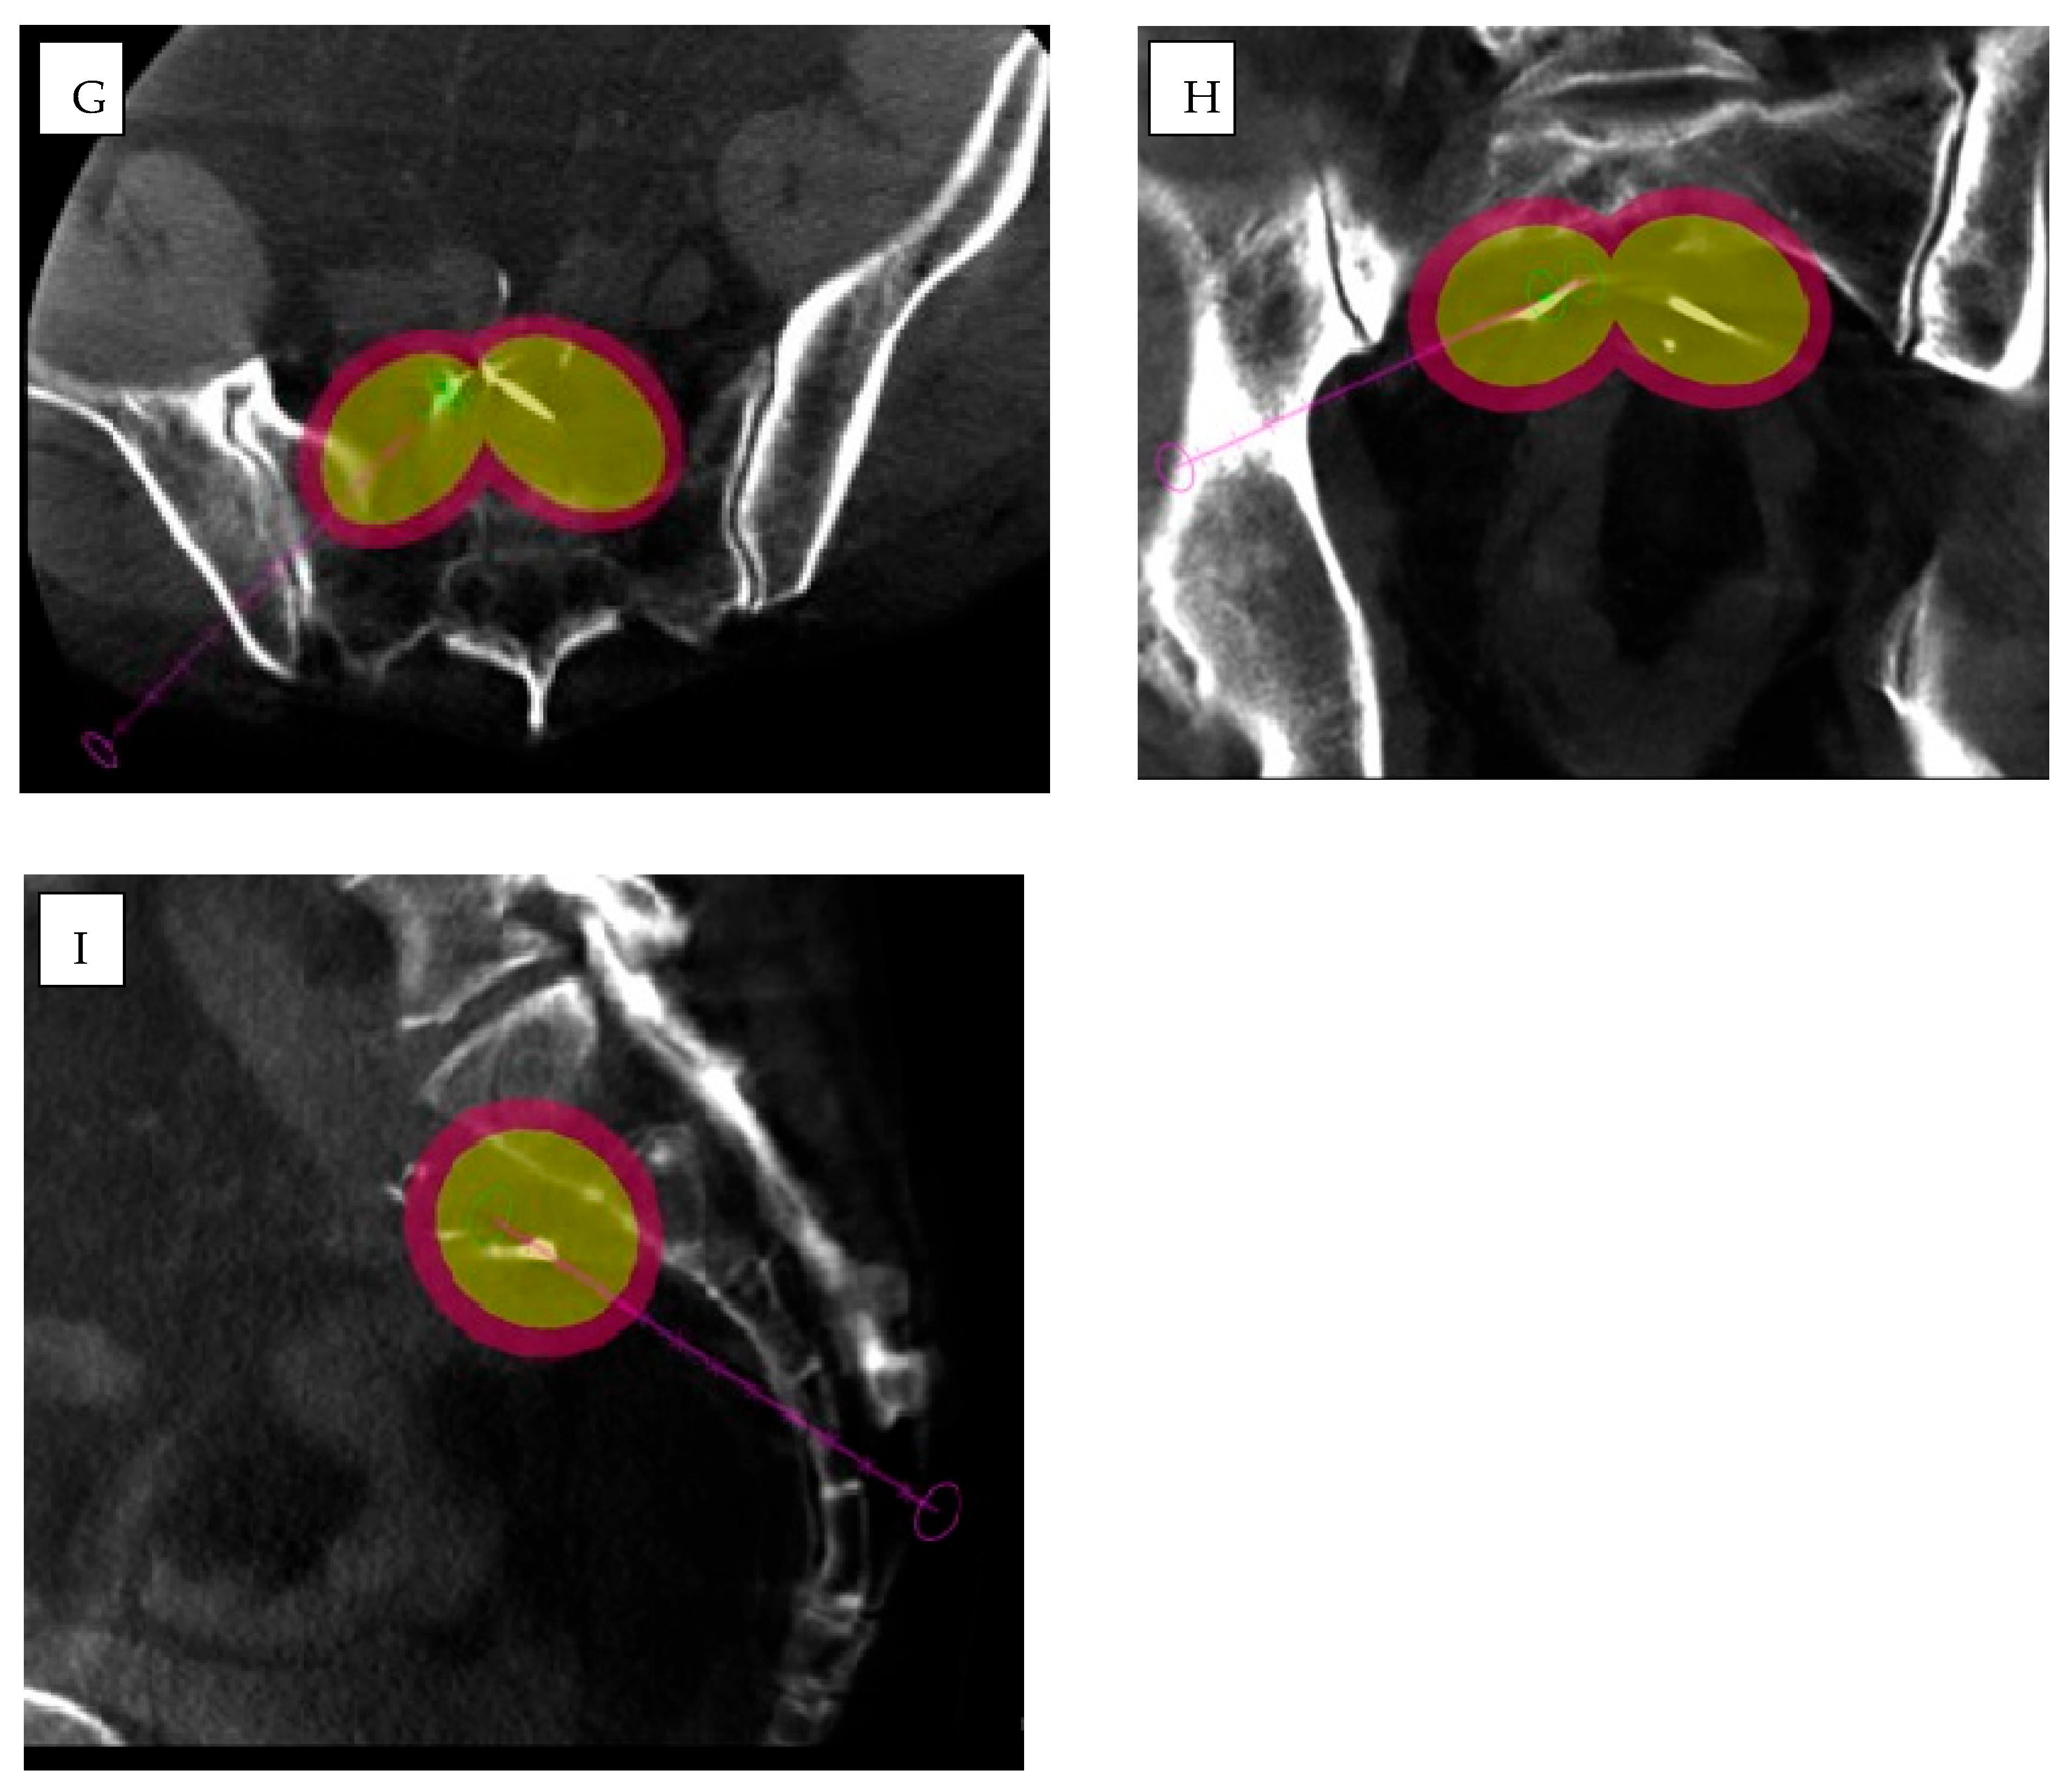

- Biondetti, P.; Ierardi, A.M.; Casiraghi, E.; Caruso, A.; Grillo, P.; Carriero, S.; Lanza, C.; Angileri, S.A.; Sangiovanni, A.; Iavarone, M.; et al. Clinical Impact of a Protocol Involving Cone-Beam CT (CBCT), Fusion Imaging and Ablation Volume Prediction in Percutaneous Image-Guided Microwave Ablation in Patients with Hepatocellular Carcinoma Unsuitable for Standard Ultrasound (US) Guidance. J. Clin. Med. 2023, 12, 7598. [Google Scholar] [CrossRef]